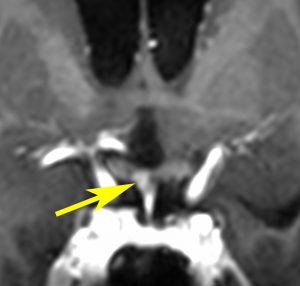

血清HCGが2.1mIU/ml,尿崩症で発症した思春期男児です。石灰化はありませんし,脂肪組織なども混在しません。生検術をしなくてもgerminomaと診断できます。でも簡単なので,経鼻的な生検術を行った方がいいです。

この例は18歳,HCG 0.1mIU/ml,尿崩症で発症しました。神経下垂体ジャーミノーマなので,下垂体前葉のみが残って後葉から視床下部が腫瘍化しています。よくよく見ると松果体にもごく小さな腫瘍があります。右のCISS画像で松果体の腫瘍化が明瞭です。

経鼻生検術で下垂体後葉部分がgerminomaということを確認してからICE (IFO/CDDP/VP-16)を1コース加えて3週間後の画像です。腫瘍は灰白隆起の部分を残してほぼ消失しています。松果体部の腫瘍も消えています。典型的なgerminomaの化学療法反応性を示しています。下垂体前葉機能は正常,尿崩症も少し良くなりました。